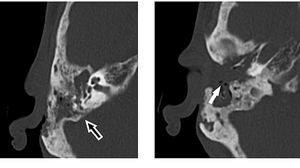

Merinding! Dokter Temukan Banyak Belatung Bersarang di Telinga Pria Ini